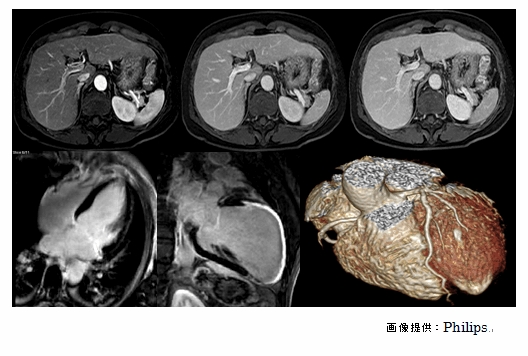

Philips社製 Ingenia 1.5T

一般的な1.5T装置よりも強い

信号を得ることができるため、

より高精細な画像を撮像できる

最高位のMRI装置です。

・頭部・腹部・四肢など幅広い領域の検査を行っています。

・心臓に負荷をかける特殊検査を行っています。